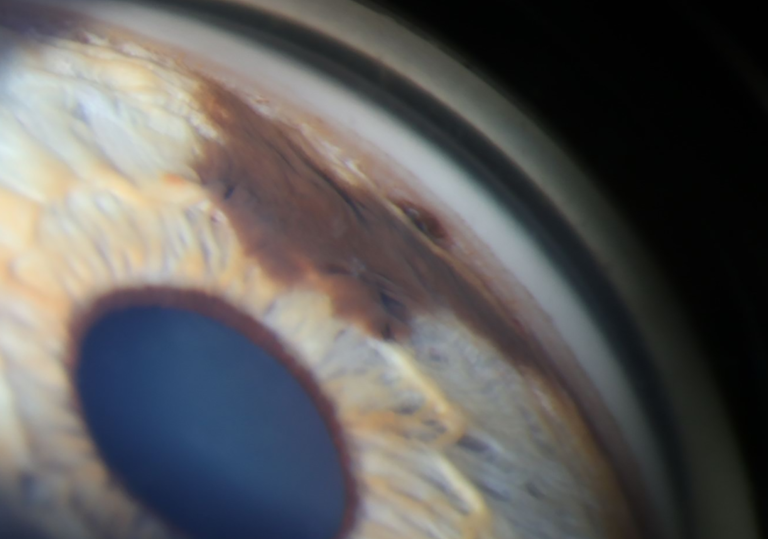

Iris Melanoma

Presented by Stephanie Burke, MS, CRA, OCT-CThis photograph received 3rd Place in the category "Gonio Photography" and was displayed at the 2024 ASCRS/OPS Society Exhibit.